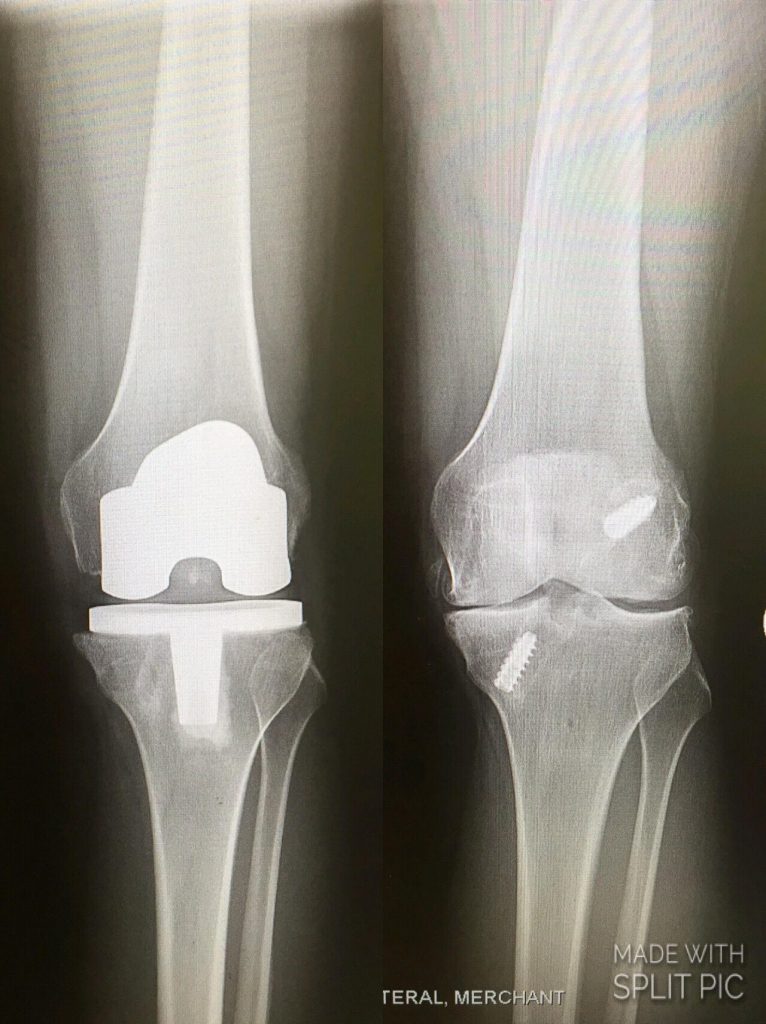

Thank you from the bottom of my heart, Dr. Sculco, for giving me my quality of life back and performing an incredibly successful total knee replacement on this unusually young patient. These past six years dealing with seven prior surgeries and regenerative stem cell procedures first due to injury, and then life-threatening infection as a complication from lupus, have been so hard on my physical and mental well-being. Now, I can finally start feeling and living like a real twenty-something. Thank you for not being afraid of my complicated case and my young age to give me this surgery, and going in with such confidence and compassion that is often hard to find. I am currently 3.5 months out of surgery and doing the unimaginable; fully functional, lifting weights, and now attending graduate school in New York City where before, I could barely make it up a set of steps or walk around the block. I'm honored to have been treated by the Surgeon-in-Chief Emeritus of this world renowned hospital and I am truly blessed. Cheers to a new life, a new knee, and being pain free.